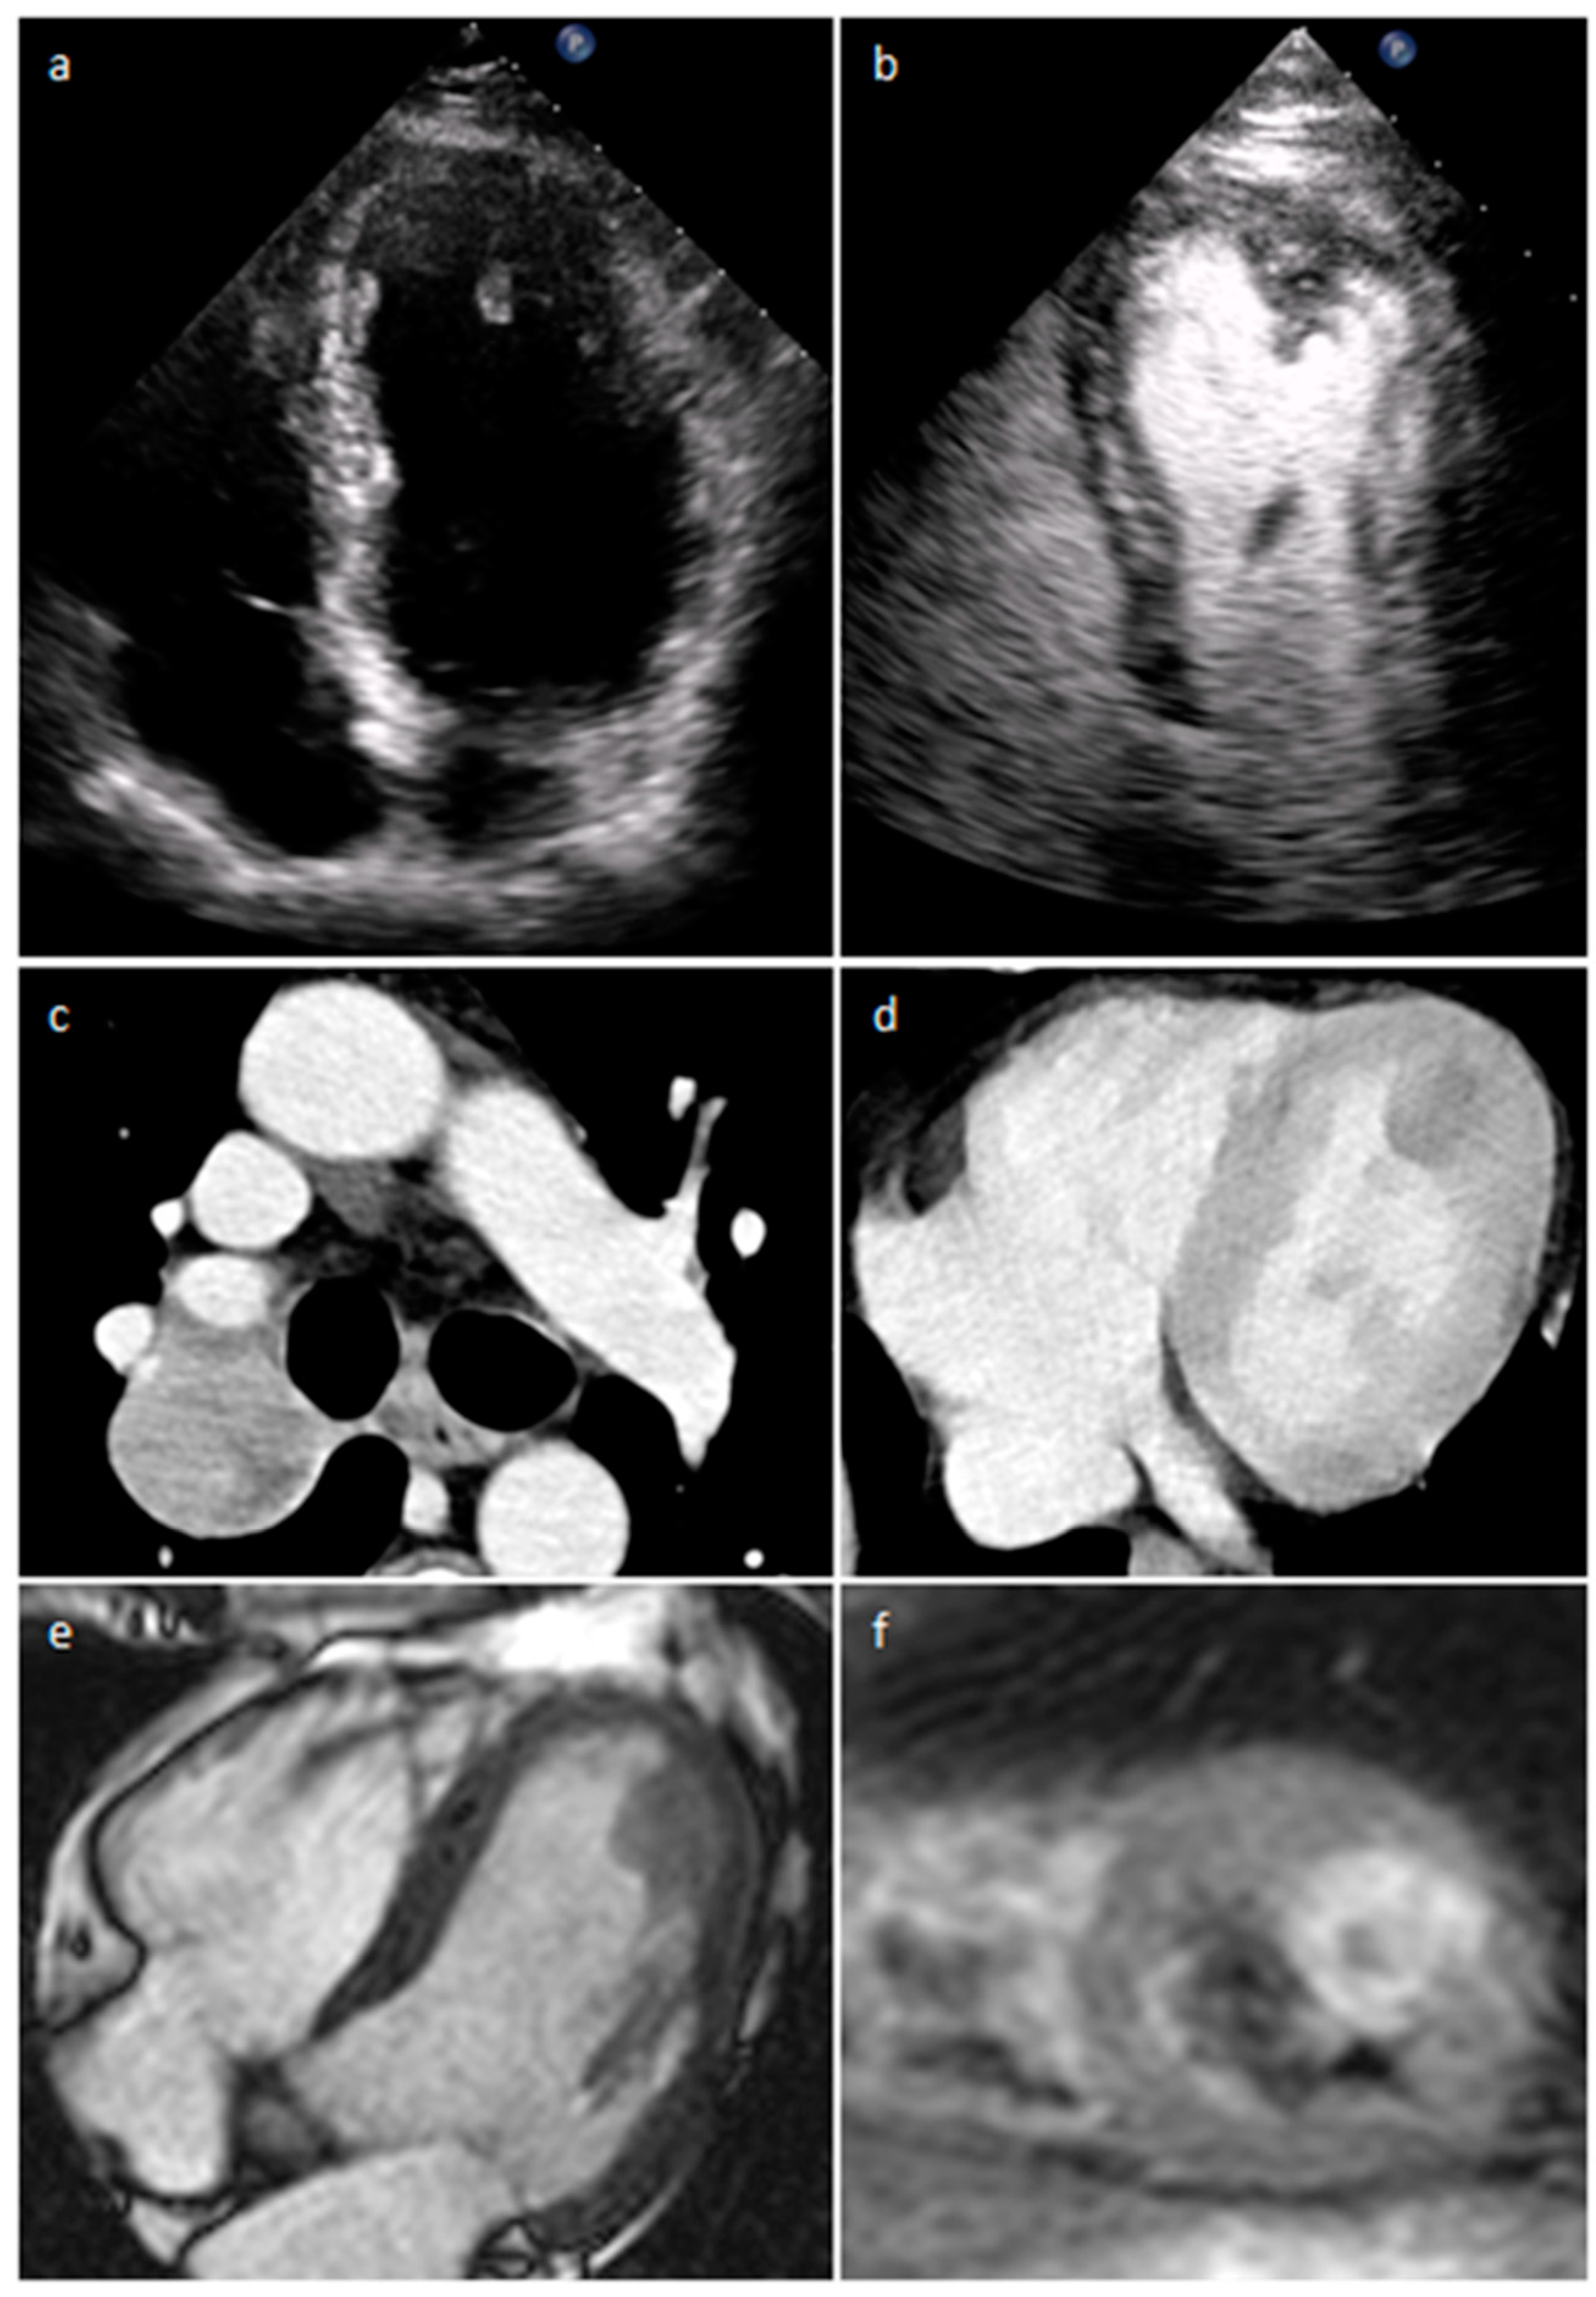

4.12. Paraganglioma

- Carvalho, J.G.; Gho, J.M.I.H.; Budde, R.P.J.; Hofland, J.; Hirsch, A. Multimodality Imaging of Cardiac Paragangliomas. Radiol. Cardiothorac. Imaging 2023, 5, e230049. [Google Scholar] [CrossRef]

| Paraganglioma | Adulthood | On the roof of left atrium, right atrioventricular groove | elevated blood pressure and severe headaches | “salt and pepper” appearance, highly vascular, parasitizes blood supply from coronary arteries, elevated serum metanephrines Malignant up to 25% | Solid heterogeneous echogenic mass with clear boundaries, and detectable blood flow signals inside it in the color Doppler | A mass of soft-tissue density with homogeneous (smaller lesions) or peripheral (larger lesions with hemorrhage, necrosis and cystic degeneration) enhancement | Iso-hypo T1w, hyper T2w, peripheral LGE. Perfusion imaging shows strong enhancement |